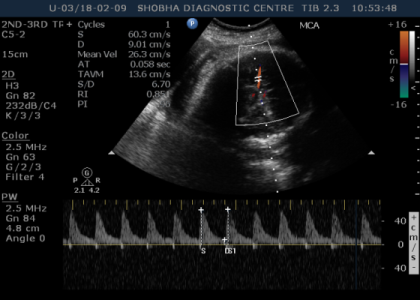

DOPPLER SONOGRAPHY / BIOPHYSICAL PROFILE

- Doppler Sonography gives information about blood circulation of the fetus.